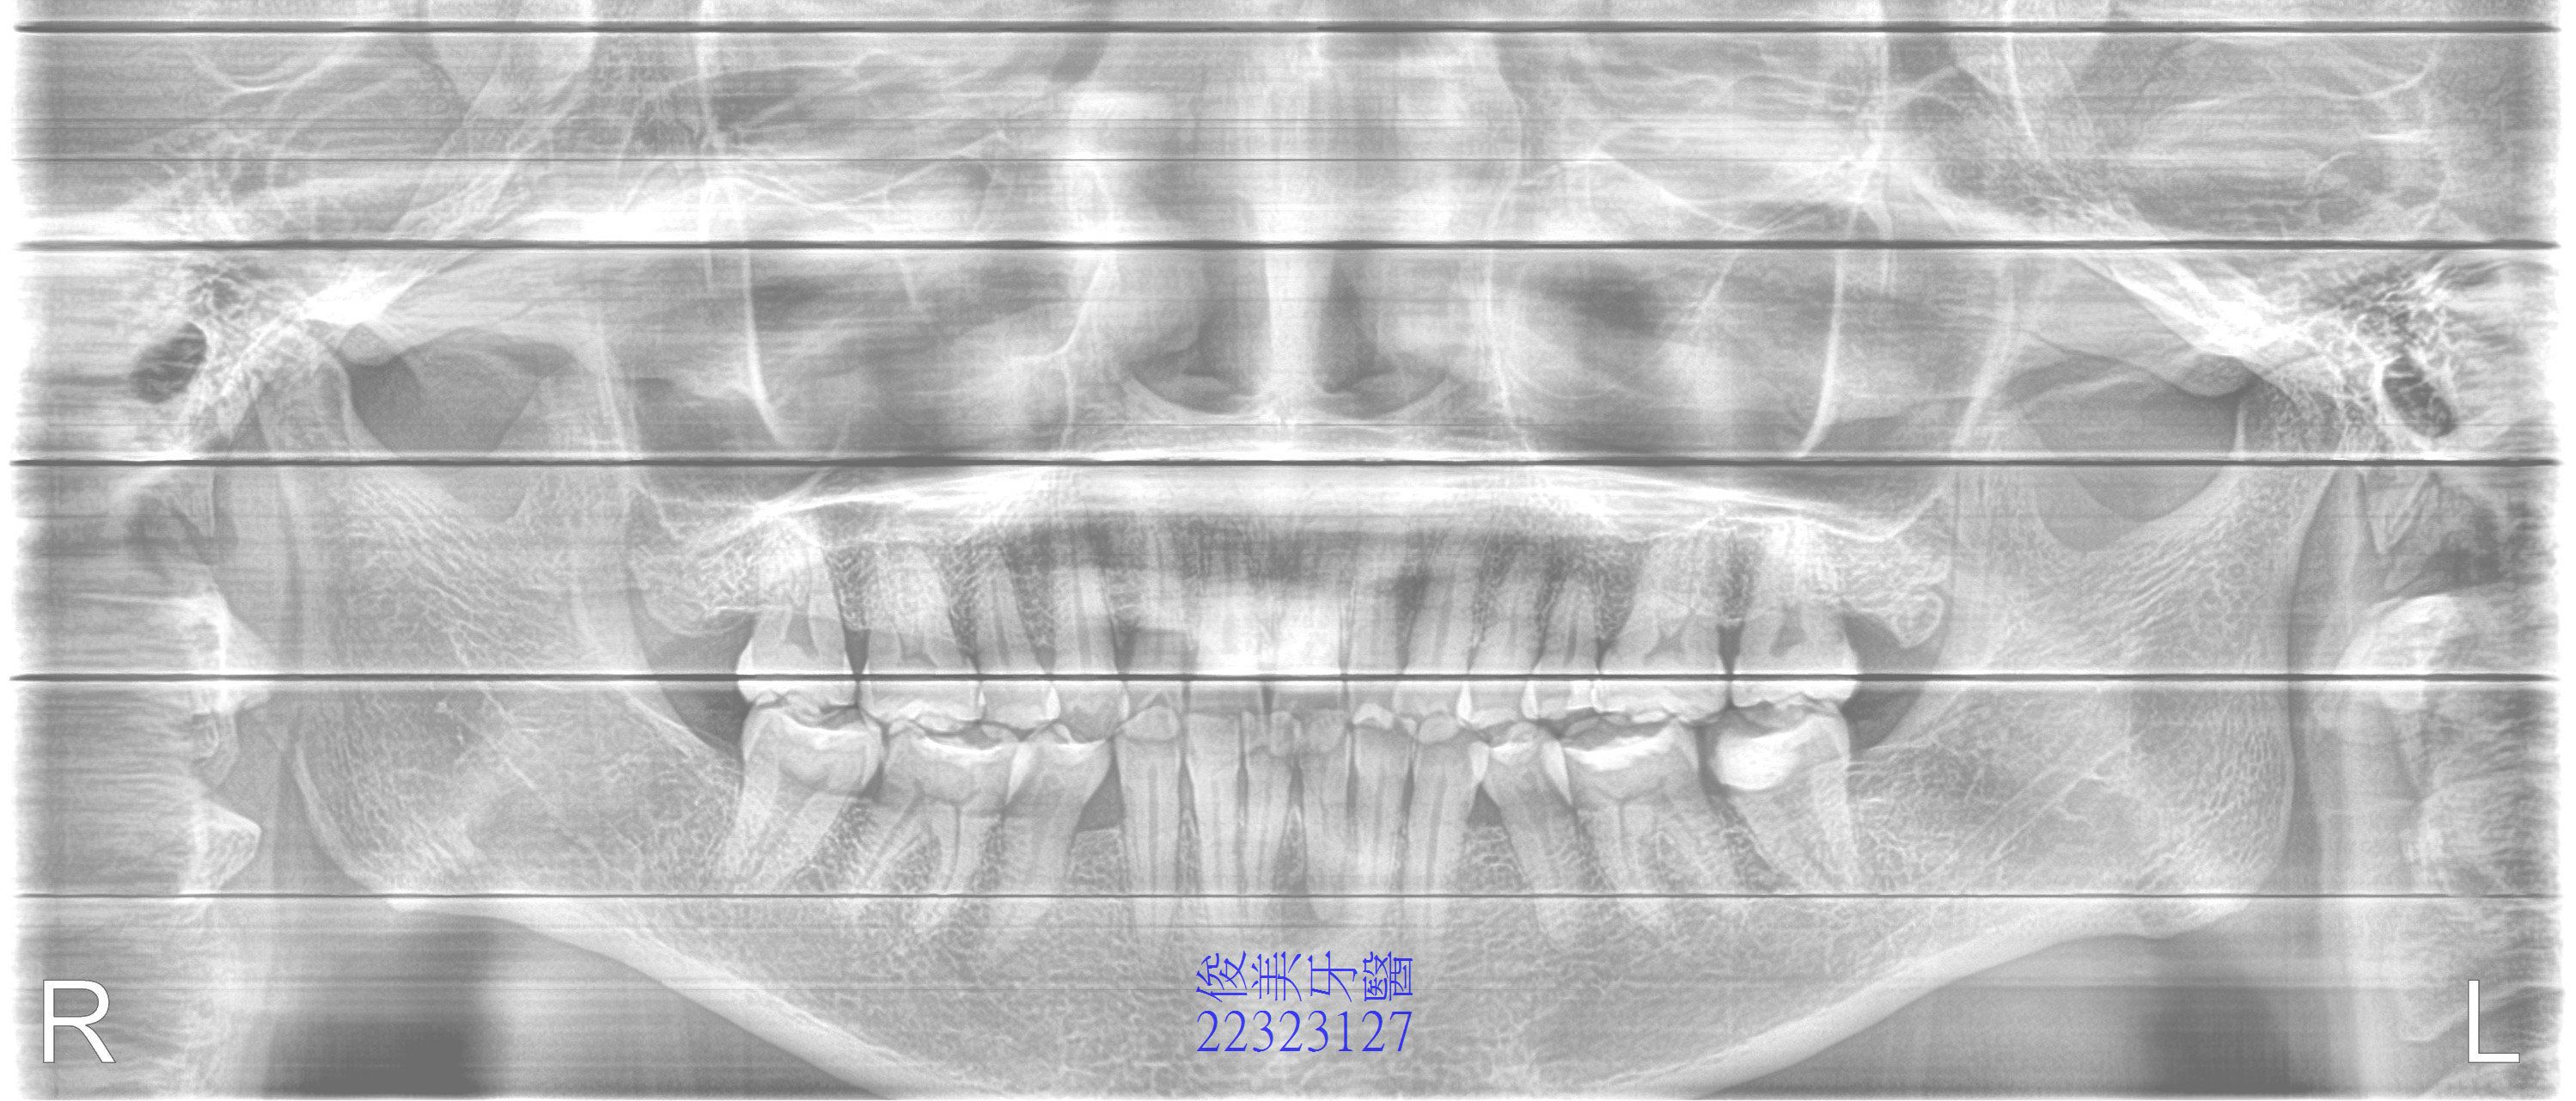

患者前牙已有不規則缺損、左右明顯不對,比例分配較不均,後牙嚴重傾倒和磨損。

牙弓明顯歪一邊。

後牙傾倒、前牙受力過大,牙齒磨損到只剩2/3顆以下。

治療中......建立後牙高度,恢復牙弓正常形狀, 小臼齒空間出來後,在正確的位子補足缺牙數量。